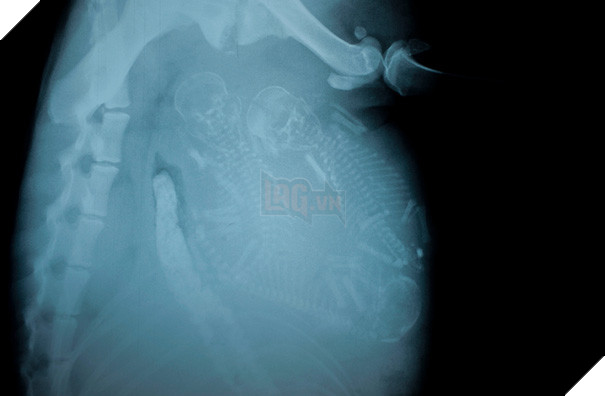

Hình ảnh trông kỳ lạ và cực khó đoán như thể một con vật 4 chân nào đó mang thai em bé. Tuy nhiên, đây là ảnh chụp X-quang một con voọc đen má trắng (khỉ Francois) mang thai.